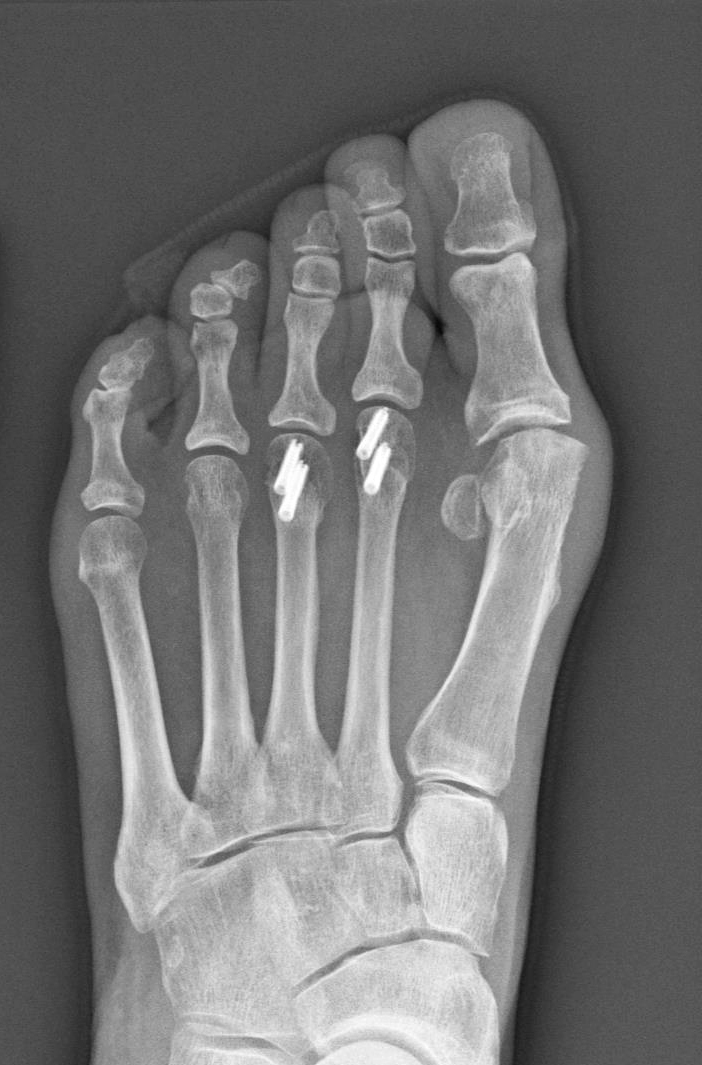

An X-ray of Sherry Young’s foot shows the four implanted screws — each of which cost more than a high-end computer.

Total Bill: $115,527 for a three-day hospital stay, including $15,076 for four tiny screws — measuring 2.8 millimeters wide and no more than 14 millimeters long — placed in the two middle toes of her left foot.

Medical Treatment: Young underwent two operations on the same day in June 2017. One surgeon addressed an injury in Young’s shoulder, caused by arthritis and overuse. A second surgeon performed several procedures on her foot, including removing a bone spur. To better align Young’s middle toes, the doctor removed a slice of bone from the center of each toe, and then reconnected the two ends with surgical screws made by Arthrex, a medical device manufacturer based in Naples, Fla.